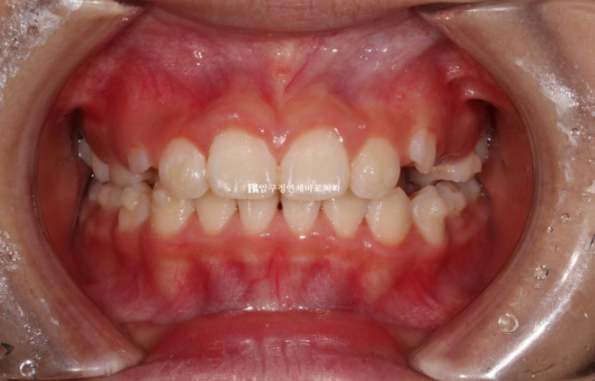

깊게 물리는 과개교합은 해소가 되었고 중심선도 잘 맞습니다.

배열은 상당히 가지런해졌고 그 사이 유치가 여러개 빠지며 영구치가 내려오는 중입니다.

재제작 총 2번 했고 토탈치료기간은 2년 중간에 쉬는 시간은 5개월 이었습니다.

치료 종료 시점 유치는 2개가 남아있었고 공간이 충분하여 아직 나오지 않은 계승영구치도 예쁘게 내려올 것으로 예상이 됩니다.

악궁확장으로 넓어진 악궁, 그리고 가지런해진 앞니가 눈에 띕니다.

중심선도 정확히 맞고 과개교합도 해소가 되었습니다

이정도 결과가 나오면 성인이 되어서도 굳이 교정을 안해도 됩니다.